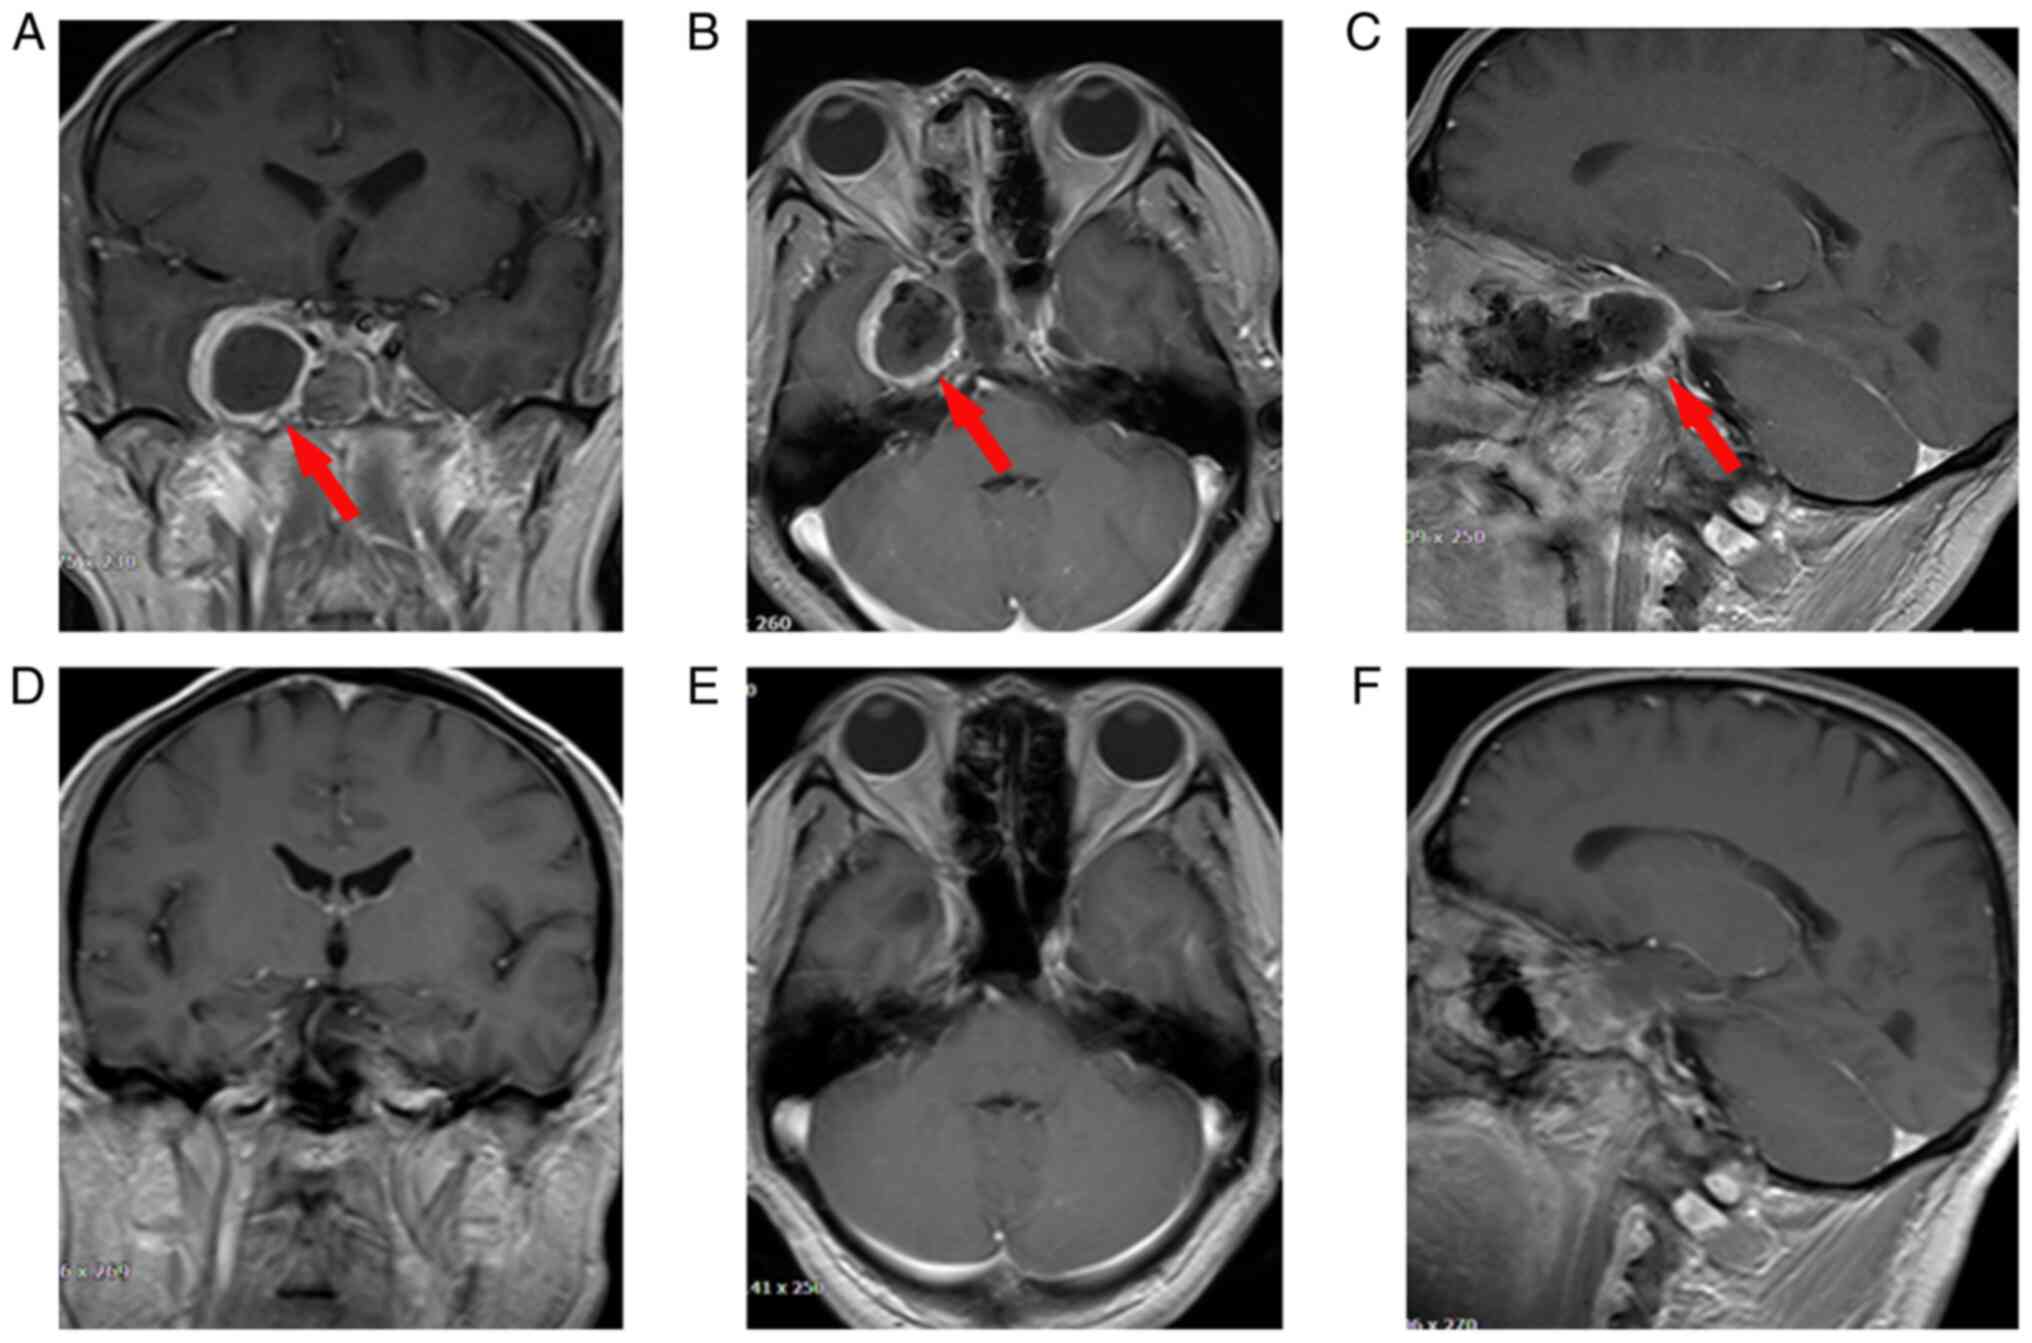

The patient who underwent TS resection via the transnasal maxillary sinus approach experienced headache relief without cerebrospinal fluid (CSF) leakage and ocular movement function disorder. The patient complained of light numbness in the distribution area of the maxillary nerve of the right side of their face, which was gradually relieved during the follow-up. An MRI conducted 1 week after the operation showed that the TS was totally resected without destruction of the sphenoid sinus and intracranial hemorrhage. The residual cavity of the TS was covered by a layer of edema tissue that displayed a higher T2 signal caused by inflammatory responses. The anatomical structure of the brain returned to normal 3 months after the operation (Fig. 3). At the last follow-up, the TS had not relapsed. Self-healing trigeminal neuralgia and paresthesia occasionally occurred in the patient during the follow-up; however, the patient returned to normal life without other symptoms. Postoperative histological analysis illustrated that the tumor was spindle-shaped and arranged in a fence-like manner without karyomitosis, and immunohistochemical staining showed that the TS was positive for SOX-10 and S100, and negative for progesterone receptor (PR). Few cells exhibited CD34 positivity. The Ki-67 labeling index of TS was 1% (data not shown). These findings confirmed that the lesion was a cellular schwannoma that arose around the cavernous sinus (Fig. 4A-D). Written informed consent was obtained from the patient to publish this case report and the accompanying images.

Figure 3

Post-operative imaging. A and D coronal sections, B and E transverse sections and C and F sagittal sections. (A-C) MRI scans taken 1 week after the operation, which indicated that the TS was totally resected without destruction of the sphenoid sinus and intracranial hemorrhage. The posterior wall of the maxillary sinus was removed and the residual cavity of the tumor was covered with a circle of T2 high signal intensity (red arrows indicate the T2 high signal intensity). (D-F) MRI scans taken 3 months after operation, which indicated that the TS residual cavity and the T2 high signal circle had disappeared. The anatomical structure of the brain returned to normal. MRI, magnetic resonance imaging; TS, trigeminal schwannoma.